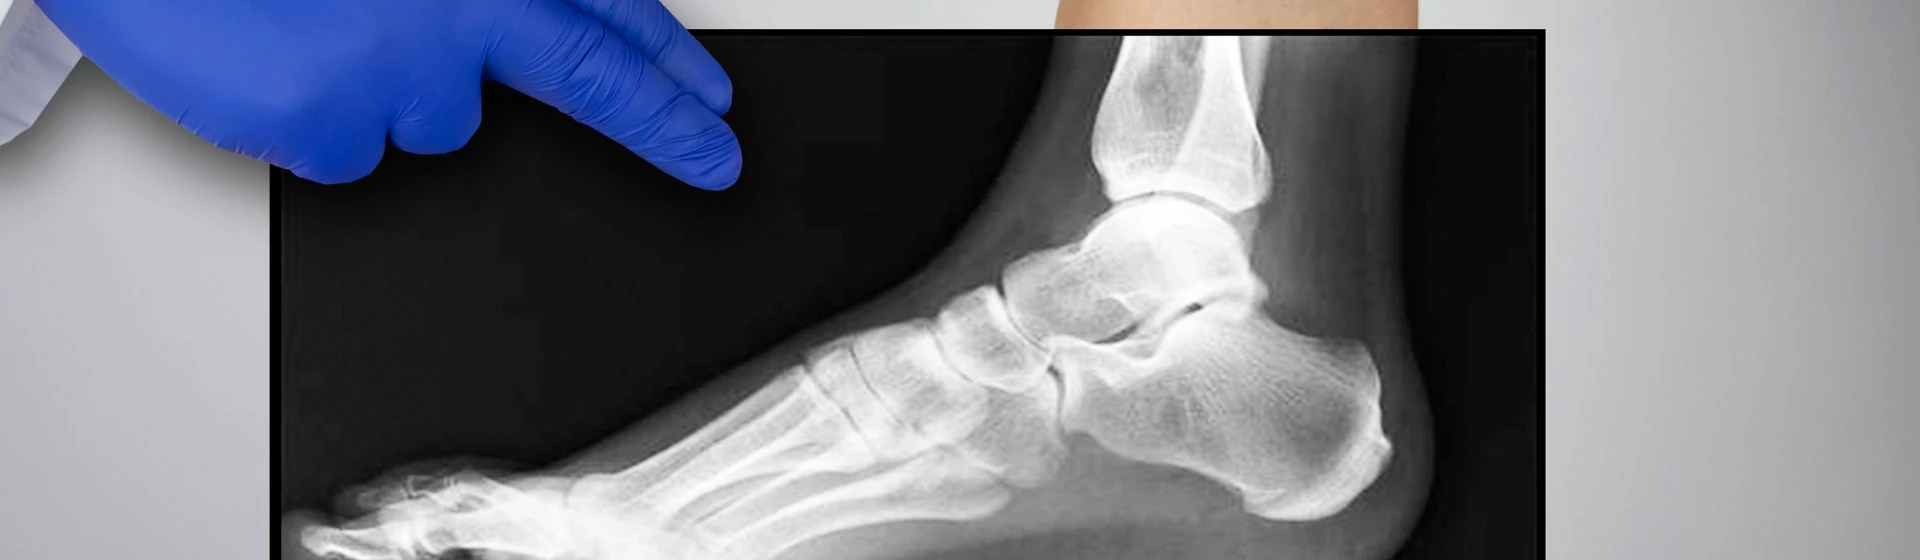

Цифровая рентгенография суставов – ведущий метод диагностики нарушений костно-суставного аппарата, применяемый при постановке диагноза, проведении дифференциальной диагностики, выборе тактики лечения (оперативная или консервативная) и контроле его эффективности.. В клинике «Оксфорд Медикал Киев» проводится рентгенография тазобедренных, коленных, локтевых, лучезапястных, плечевых, голеностопных, височно-нижнечелюстного и других суставов. Все исследования проводятся с помощью немецкого цифрового рентген-аппарата Siemens Multix Select DR.

Рентген стопы

Делают в 2 или 3 трех проекциях, чтобы оценить состояние всех костей и суставов. По его результатам можно диагностировать вывихи и переломы, плоскостопие, пяточную шпоры и другие патологии.